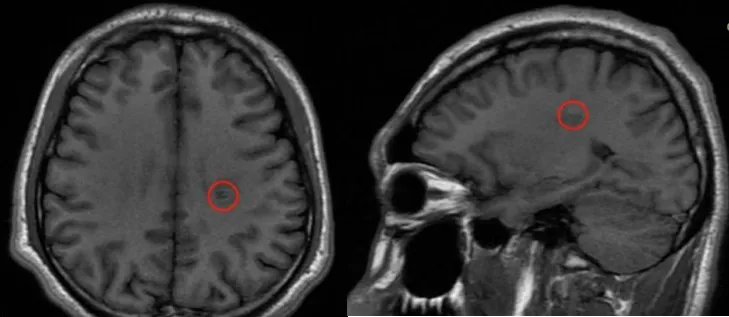

术后核磁共振检查结果好,病灶完全切除,周围区域也很干净。因此,手术目标已经完全达到。下一次核磁共振检查应在一年后,即2025年春季进行。

2024年4月,我们也收到了巴教授发来的随访邮件,在查看了斌斌术后一年核磁影像后,巴教授回复目前斌斌的情况好,肿瘤全切一年后没有复发。

术前术后MRI影像对比